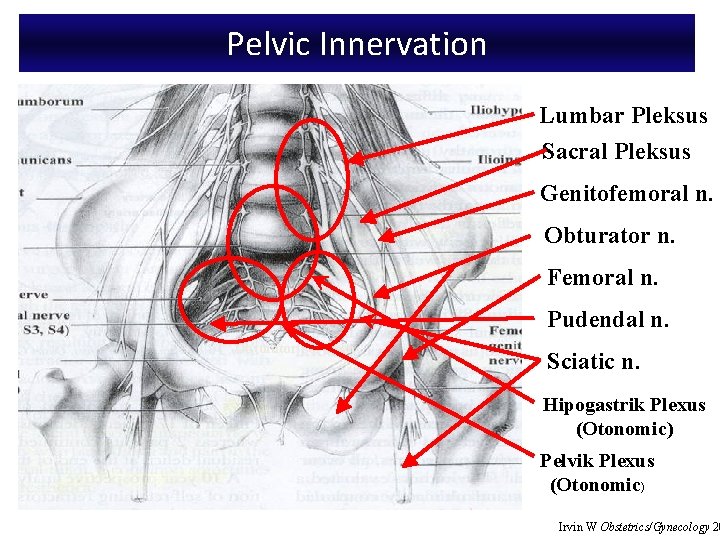

Anatomy: Pelvic Innervation • Pelvic splanchnic nerves from 2 nd to 4 th sacral nerves • Pudendal nerve supplies vulva and lower vagina

Pelvic Innervation Lumbar Pleksus Sacral Pleksus Genitofemoral n. Obturator n. Femoral n. Pudendal n. Obturator Foramen Sciatic n. Hipogastrik Plexus (Otonomic) Pelvik Plexus (Otonomic) Irvin W Obstetrics/Gynecology 20